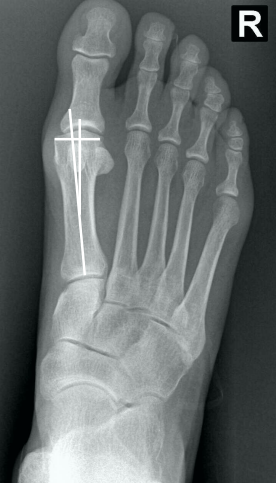

• Como verificar na radiografia AP com carga, se há luxação do sesamóide e classifica-lo de acordo com Mann e Coughlin?

• Traça-se um linha no eixo do 1° mtt e verifica o quanto, em “%”, a linha toca o sesamóide tibial (medial)